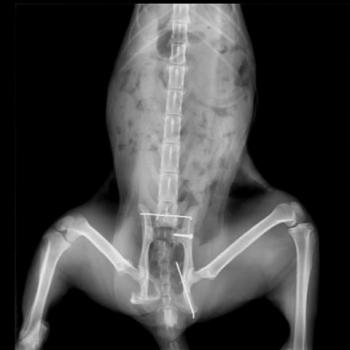

Lin tauchte plötzlich in der Nähe einer der betreuten Kolonien auf. Da er die Hinterbeine nachzog, wurde er eingefangen und in die Tierklinik gebracht. Beide Hüften waren gebrochen, sind aber inzwischen operiert worden. Er ist jetzt zur Genesung in einem Käfig untergebracht. Momentan ist Lin noch sehr misstrauisch, wir hoffen aber, dass er sich entspannt, wenn er merkt, dass die Tierschützer es gut mit ihm meinen.